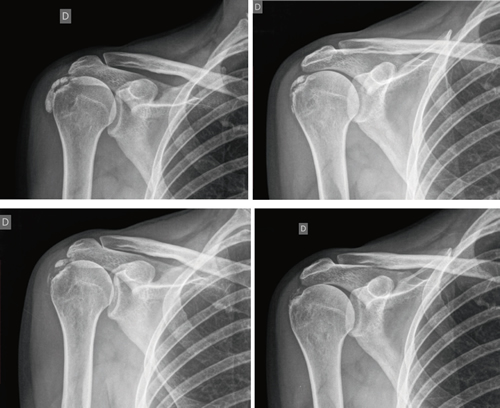

The average number of sessions in our series was 20. The criteria for continuing or stopping treatment was the radiological and clinical evolution (Figures 4 and 5). The interventions were performed up to a maximum of 40 sessions. Perrón treated patients for 9 sessions (3 weekly sessions for 3 weeks) (14). Leduc treated with 10 sessions (3 per week for the first two weeks; then one weekly for 4 weeks) (15). Rioja-Toro treated patients for 40 sessions (5 times per week) and evaluated them at 20 and 40 sessions (3). Chico-Álvarez treated patients between 15 and 30 sessions depending on the radiological evolution (5 times per week) (1).

Fig. 4. 47-year-old female patient with formative right supraspinatus calcific tendinitis who, after 30 sessions of iontophoresis, decreased pain measured by VAS from 6/10 to 3/10 and calcification from 38 mm to 8 mm (assessments at onse and at 10, 20 and 30 sessions, respectively).